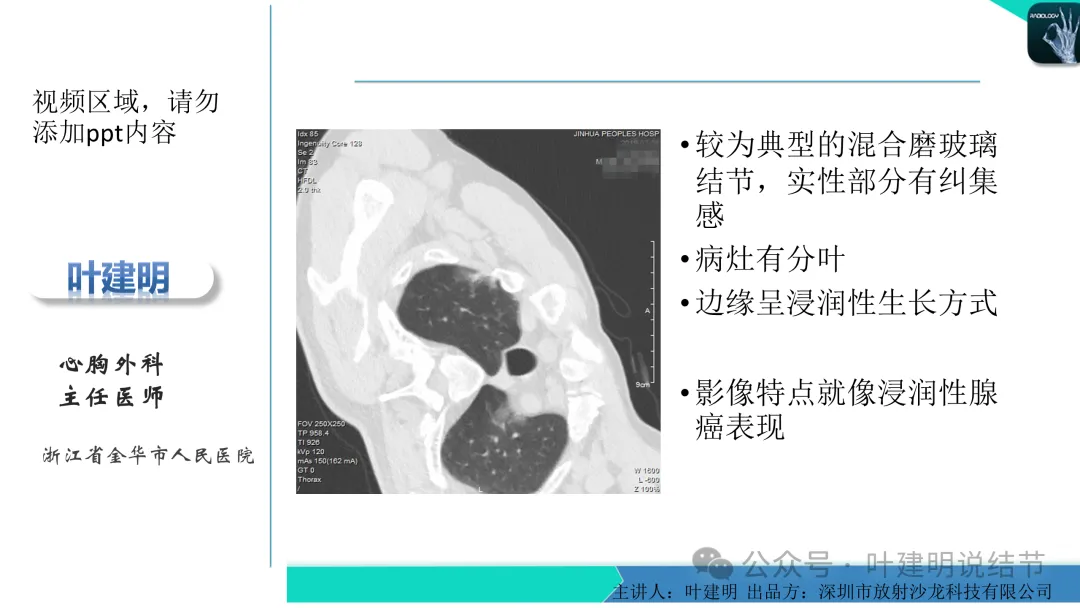

早在2020年时,我受邀在《放射沙龙》做过一个系列的精品课,当时专门总结分析过各类良恶性肺结节与肿块的影像特征,这是当时关于微浸润性腺癌影像特征的分析,今天看来仍基本不太需要改变,大家有兴趣的可以参考: